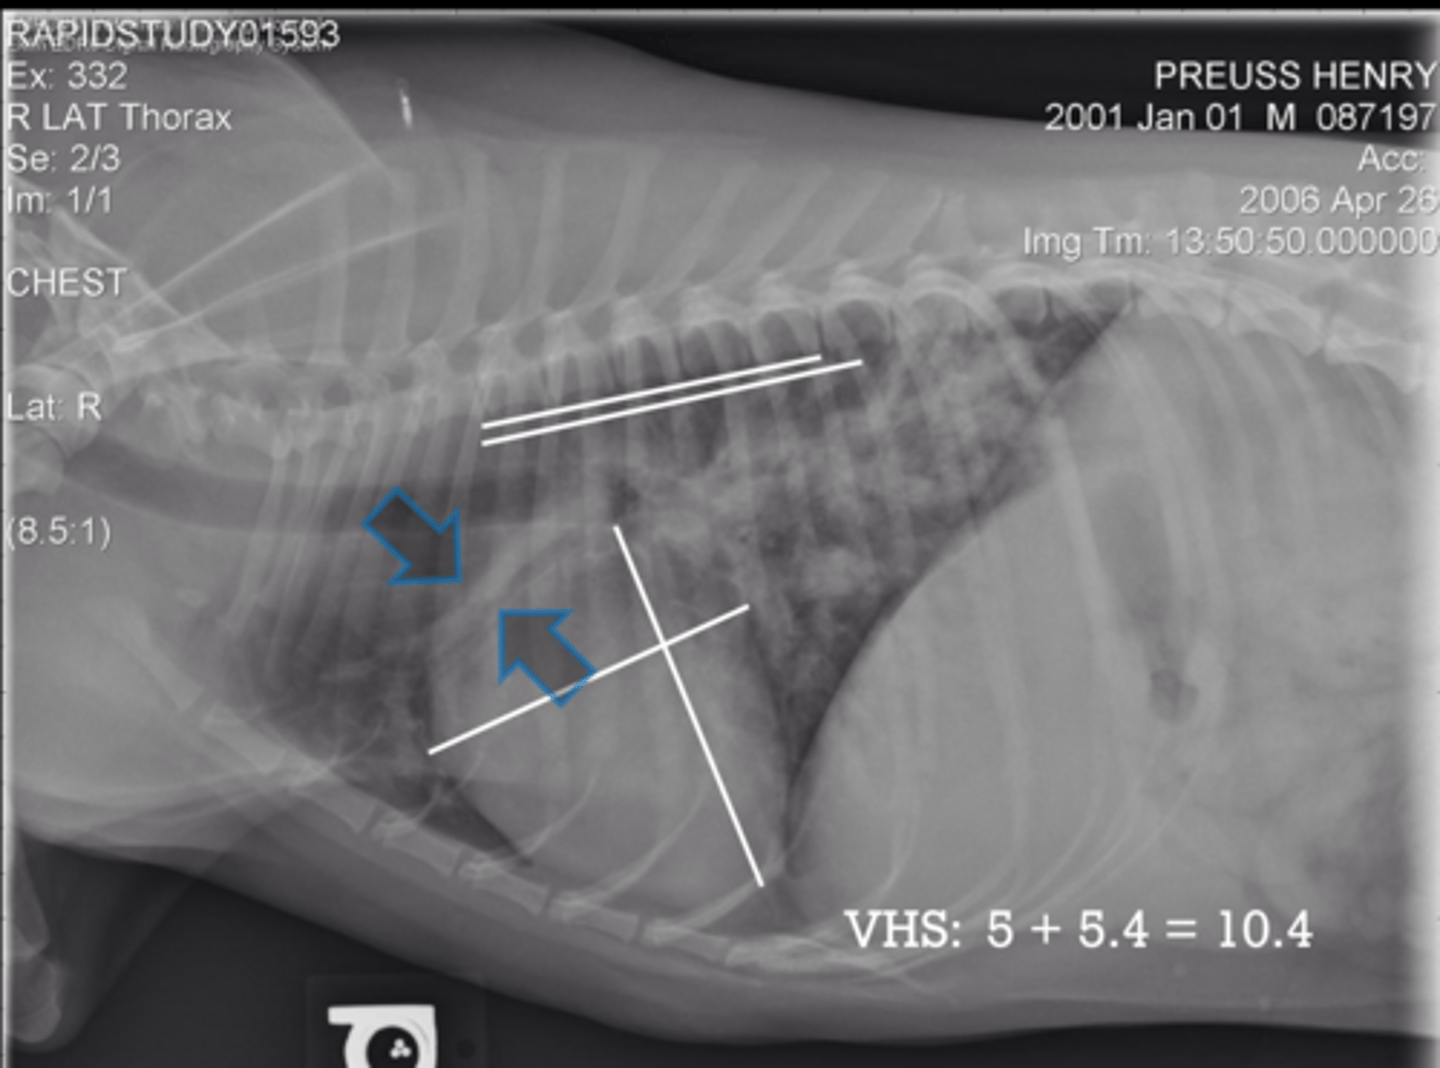

5.7 + 4.3 = 10

(K9 - 10.5)

Given the following radiograph do we have an enlarged heart?

No